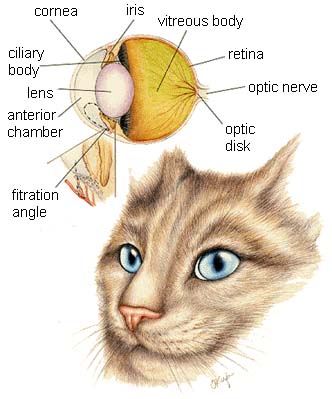

The organs of special senses allow the animal to interact with its environment; sight, taste, smell and hearing.

Cat Eyes